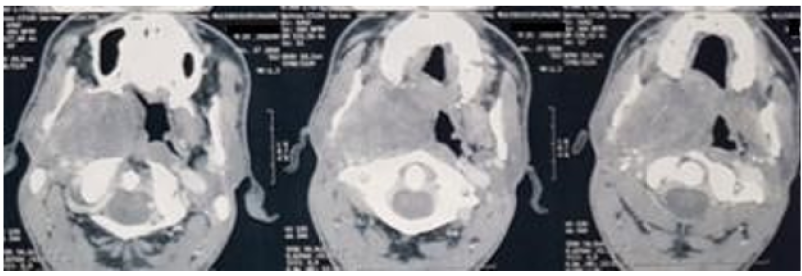

Gigantic Pleomorphic Adenoma: An Impossible Intubation? (A Case Report)

Amine Zerhouni, S Benhamza, M Lazraq, Y Miloudi, A Bensaid and N Elharrar. 6(5): 18-21.